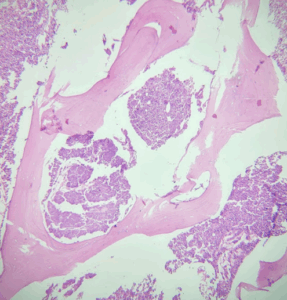

LEIOMIOMA OVÁRICO

Ver Caso